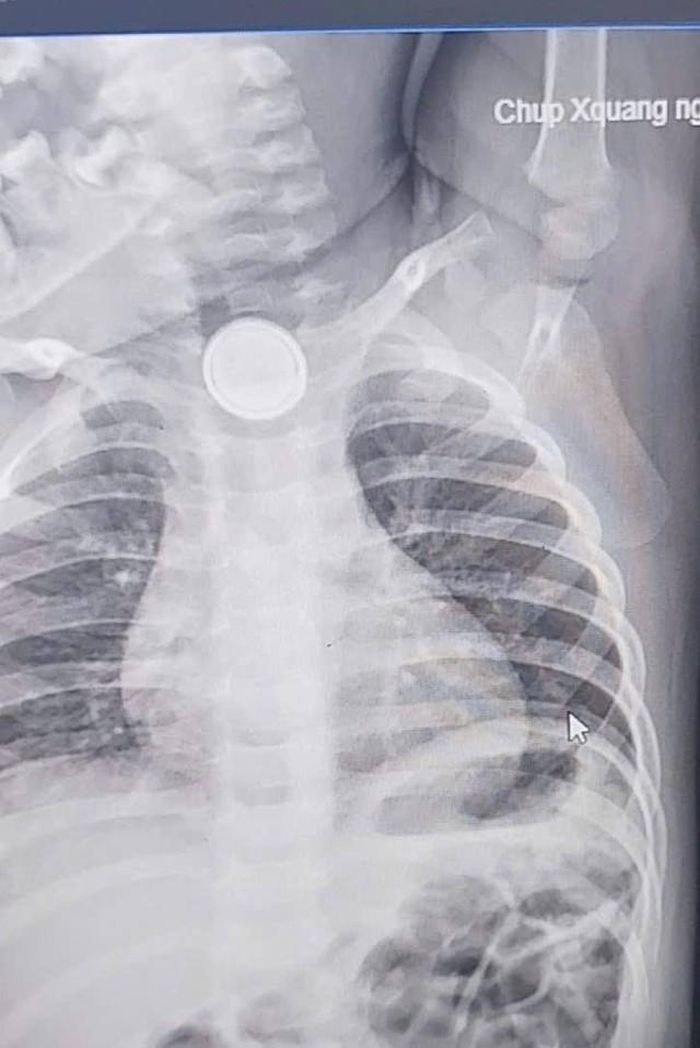

nguy hiểm khi trẻ nuốt phải pin cúc áo. Vừa qua, thông tin về một bé trai 24 tháng tuổi phải nhập viện trong tình trạng thực quản bị bỏng nặng do nuốt pin cúc áo đã khiến nhiều bậc cha mẹ không khỏi lo lắng. Đây không phải là lần đầu tiên câu chuyện đau lòng như vậy xảy ra, và nó là lời nhắc nhở mạnh mẽ rằng chúng ta cần nâng cao nhận thức và có những biện pháp phòng ngừa hiệu quả.

Như trường hợp bé 24 tháng tuổi, dù đã được gắp dị vật, bé vẫn đối mặt với nguy cơ biến chứng lâu dài. Điều này có thể bao gồm hẹp thực quản, khó nuốt kéo dài, hoặc các vấn đề tiêu hóa khác, ảnh hưởng nghiêm trọng đến sức khỏe và chất lượng cuộc sống của trẻ sau này.